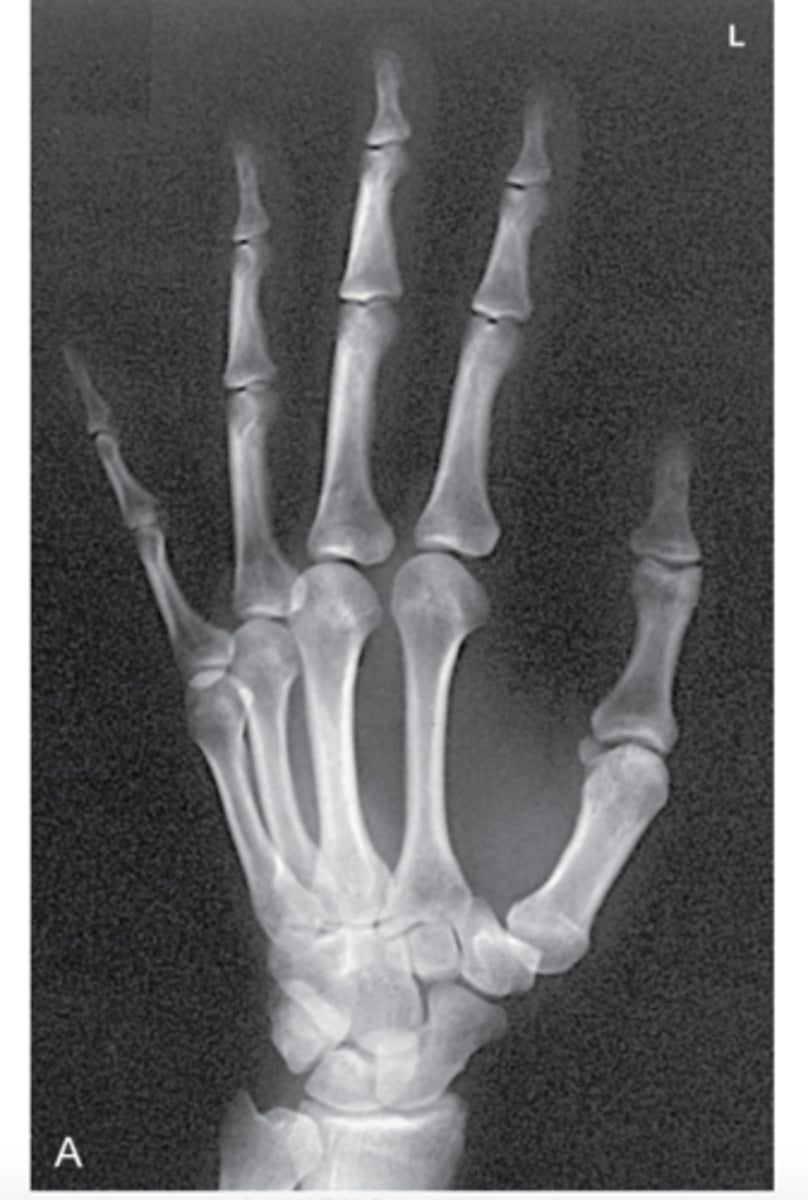

In an x-ray of a hand, the bones _________ more radiation than the surrounding tissue, therefore, they cast heavier "shadows' on the scan.

Attenuate

<p>Attenuate</p>

What color are "shadows" on x-ray film?

White

What are the 4 types of radiographic densities?

1. Gas (air)

2. Fat

3. Water

4. Bone